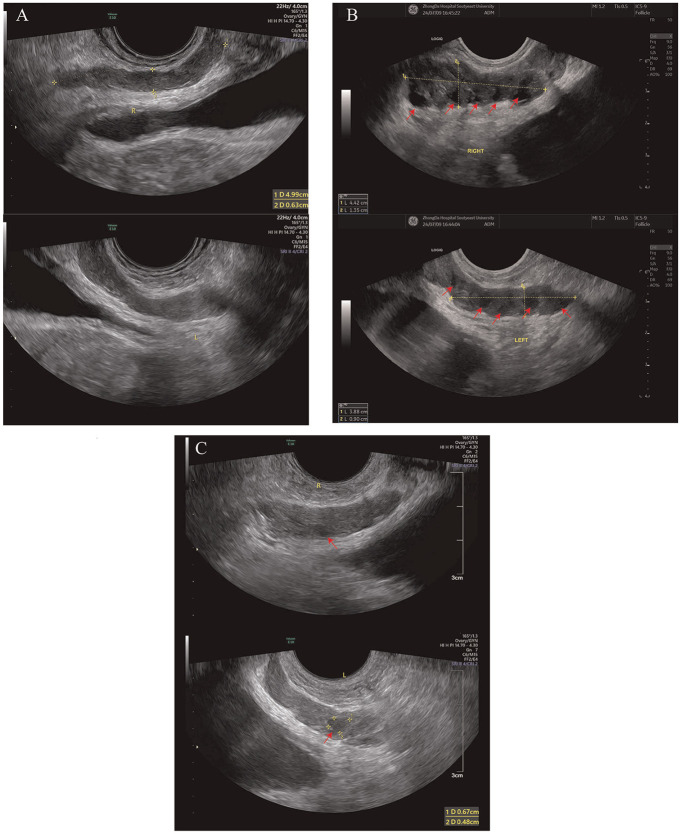

由于无精症(AE)的临床报告率低,学术界对其认识不足,因此该病长期以来一直是男性学界的难题。本病例报告讨论的是一名 52 岁的 AE 患者,长期患有糖尿病。他的精囊超声图像显示没有明显的多环状无回声区,而这一特征以前在 AE 患者中从未报道过。我们推测这一发现是由于糖尿病引起的精囊分泌功能障碍,从而导致了该患者的 AE。本病例强调了无回声多环区在射精生理学中的重要性,并突出了进一步研究这些区域与各种射精障碍之间的相关性的必要性,旨在为医学界提供有价值的见解。

Anejaculation (AE) has long been a challenging issue in andrology due to its low clinical reporting rate, leading to an insufficient understanding within the academic community. This case report discusses a 52-year-old AE patient with a long-term history of diabetes mellitus. His seminal vesicles ultrasound images revealed a notable absence of anechoic polycyclic areas, a characteristic not previously reported in AE patients. We hypothesize that this finding is attributable to diabetes-induced seminal vesicles secretory dysfunction, leading to AE in this patient. This case underscores the importance of anechoic polycyclic areas in the physiology of ejaculation and highlights the necessity for further research into the correlation between these areas and various types of ejaculatory disorders, aiming to provide valuable insights for the medical community.